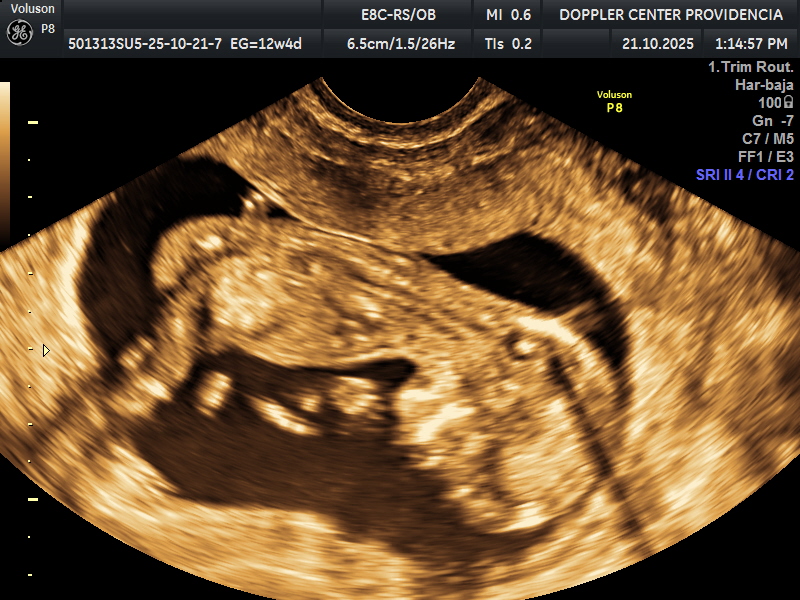

• Eco Doppler 11-14 semanas